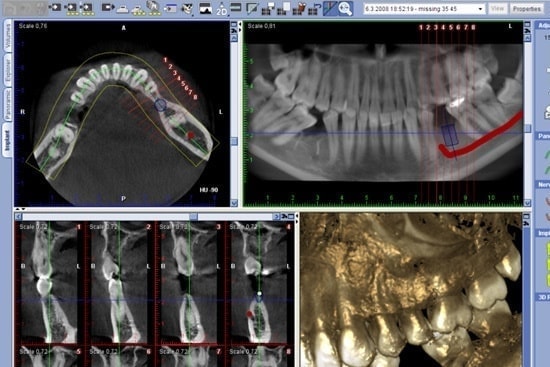

歯科用CTは、歯科用レントゲンでは見ることができない部分も立体的に映し出すことが可能です。そしてより的確な診断ができるようになります。当医院では、インプラント治療のほか、親知らずの抜歯や歯周病治療、歯の神経の治療、歯根の破折の治療、顎関節症の診断などに使用しています。撮影は座ったままで行い、時間は数十秒で終わるため、被曝線量も一般的な医科用CTの数10分の1と非常に少なく済みます。

CTを導入しているメリットとして、同じ医院内で検査から治療までできるということがあります。かつてのCTの機器は大変高額で広い部屋も必要なため、大きな病院でしか撮影ができませんでしたが、医療機器の進歩により歯科医院内での撮影が可能になり、正確な診断から治療までシームレスに行えるようになりました。これは患者様の費用負担の軽減や時間の節約になるなど、大きなメリットと言えるでしょう。基本的に歯科用CTは医科用に比べ被ばく量が格段に少なく、そしてはるかに多くの情報を得ることができます。そのため特にインプラント治療などの精密な治療が必要となる場合にも、安全性・確実性を向上できる必須のツールとなっています。

昨今のインプラント治療において、CT撮影は必要不可欠な存在となっています。インプラントを安全に骨に埋め込むには、顎の厚みや骨の密度、神経や血管の走行を3次元的に把握することが必要となります。それもかなり正確に分析できないと手術の失敗につながります。なので当然ですが当院では少しでもインプラント治療を成功に近づけるために歯科用CT撮影装置を導入したというわけです。